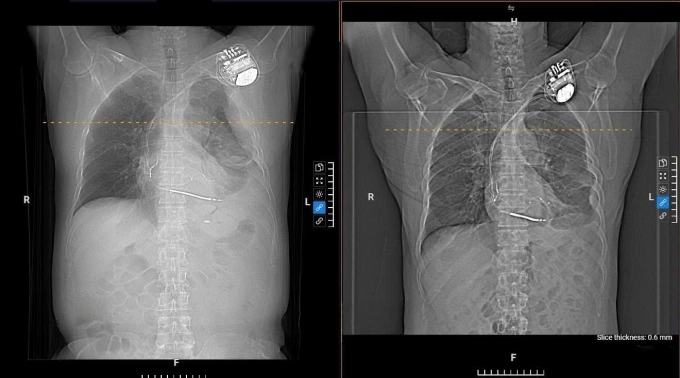

Bệnh nhân mắc các bệnh lý rối loạn nhịp tim, suy tim khá nặng và đang điều trị bằng thuốc. Thông thường, tràn dịch màng phổi, mủ tạo thành ổ khu trú như bệnh nhân này bác sĩ sẽ chỉ định phẫu thuật chọc mủ màng phổi. Tuy nhiên, ông Pirone có bệnh nền về tim mạch, ca phẫu thuật được tiên lượng nhiều nguy cơ nên phải điều trị nội khoa.

Sau 20 ngày điều trị tích cực, dịch ở phổi được cải thiện, bệnh nhân xuất viện. Tái khám sau một tuần, ông hết đau tức ngực, khò khè, hết ho đàm.